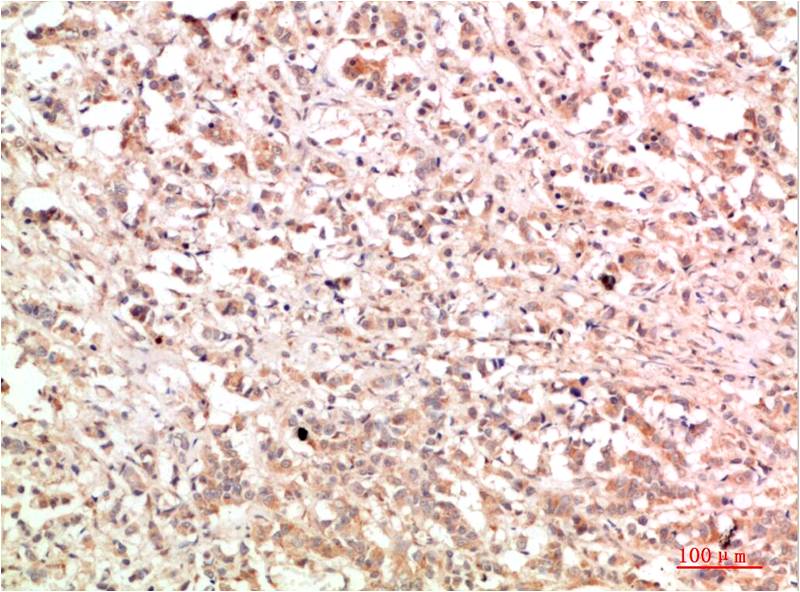

Acetyl P53(K382) Mouse Monoclonal Antibody(5H10)

Applications :IHC

p53 plays a major role in the cellular response to DNA damage and other genomic aberrations. The activation of p53 can lead to either cell cycle arrest and DNA repair, or apoptosis. Acetylation appears to play a positive role in the accumulation of p53 protein in stress response.

| Recommended dilutions: | IHC: 1:100-200 |

| Specificity: | The Acetyl P53(K382) Mouse Monoclonal Antibody can detects endogenous Acetyl P53(K382) proteins. |